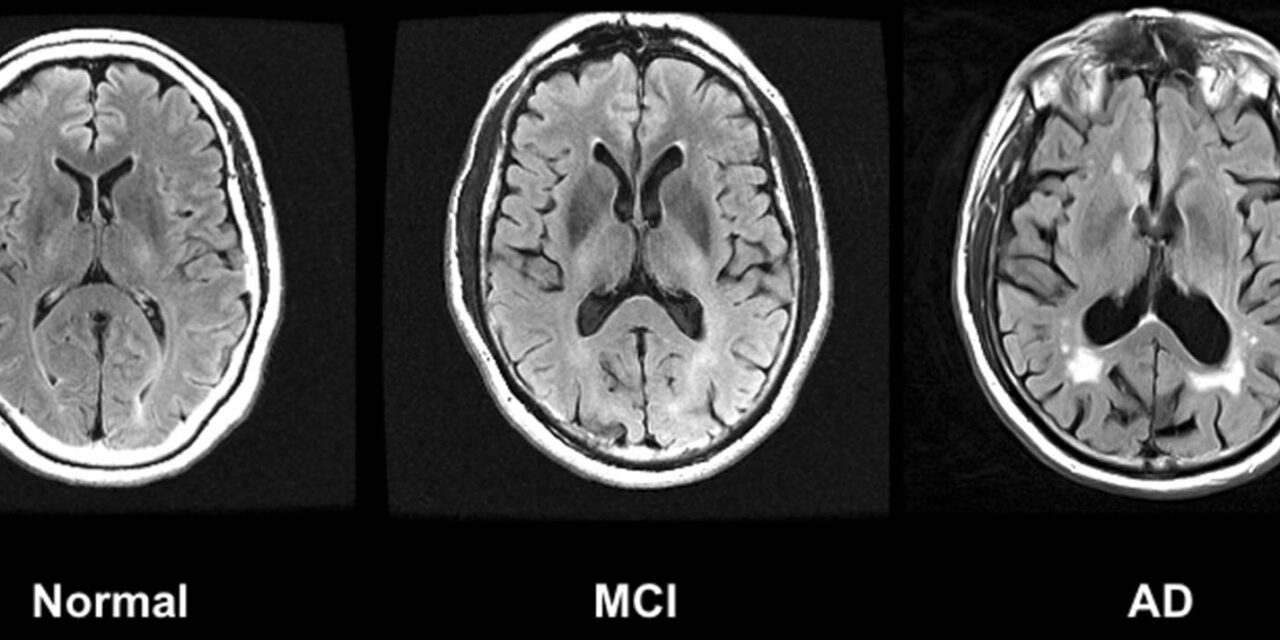

HNO Springer/Nature ■ Das Thema Demenz ist für viele Menschen mit Sorge und Unsicherheit verbunden. Gleichzeitig betrifft es immer mehr Familien und stellt unsere Gesellschaft vor grosse Herausforderungen. Wegschauen hilft...

HWB ■ Dass unser Gehör weit mehr ist als ein Sinnesorgan, wird in der Forschung immer deutlicher. Gutes Hören spielt eine zentrale Rolle für Kommunikation, soziale Teilhabe – und offenbar...